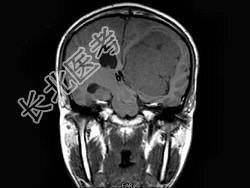

- 单项选择题男,27岁, 一过性黑矇发作半年伴记忆力下降,听觉性失语, 双眼同向性右侧视野缺损,无头痛、呕吐, MRI平扫及增强扫描,最可能的诊断为 ( )

A、侧脑室脑膜瘤

B、侧脑室室管膜瘤

C、侧脑室乳头状瘤

D、侧脑室星形细胞瘤